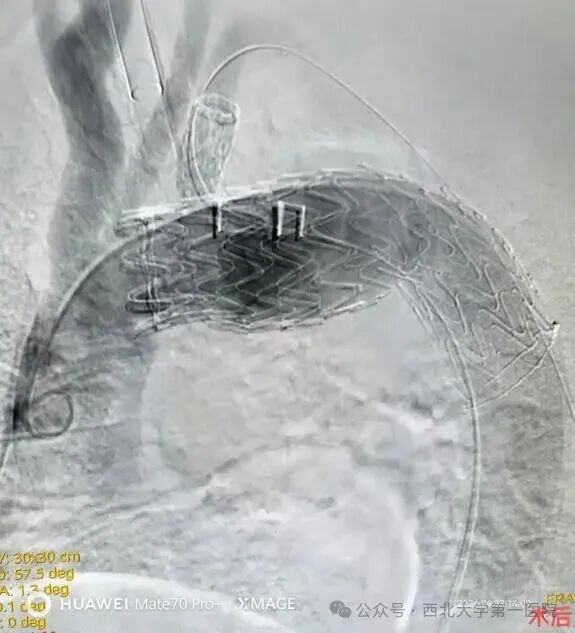

最终,由介入科副主任医师张海福带领团队,为患者实施了胸主动脉分支覆膜支架置入术。手术操作精准、过程顺利,成功解除了危及患者生命的血管病变。

腔内修复(EVAR):微创介入手术,通过放置支架隔绝瘤腔,创伤小、恢复快,是目前主流治疗方式